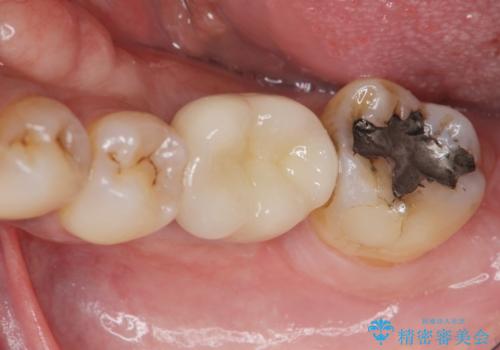

失った奥歯をインプラントで機能回復

元あった歯のようにしっかりと咬合機能が回復することができました。